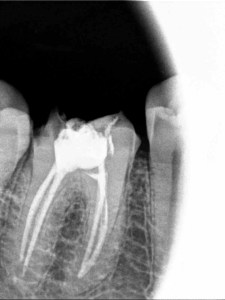

My tooth, sans roots.

dental work occurs roadside. But lo and behold, I discovered a Lebanese dentist (raised in Senegal) who operated a modern, dental practice in an actual building near our school, and he had a number of our students as patients. So off I went to have him reattach the old crown which I was sure would take ten minutes. Except the old crown was cracked and he needed to make a new one. And then he discovered that a root canal had not been done on that old tooth (thank you crappy Florida dentist).

So long story short, he did the root canal (even finding a 4th root which he said was rare), had a fancy new crown made in France, and made my mouth whole again…all at half the cost of a dentist in the U.S. My dentist in the U.S. checked his work and gave his seal of approval. However, this all took six lovely visits, some of which seemed like movie scenes: the time he and his wife/assistant had a huge argument in French during my actual root canal; our debate over whether I have a gag reflex or whether he just put too much of the molding material in my mouth because it touched my uvula, etc.).